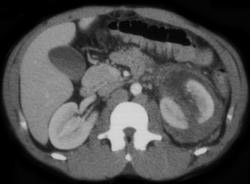

Subcapsular Hematoma